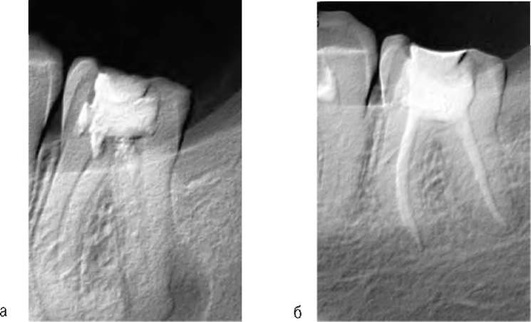

Учитывая, что клиническая картина хронического периодонтита может отсутствовать или быть незначительно выраженной для дифференциальной диагностики обязательно проведение рентгенографии. На рентгенограмме определяют деформацию периодонтальной щели с нарушением четких контуров компактной пластинки кости альвеолы. Многие случаи хронического апикального периодонтита связаны с некачественным эндодонтическим лечением (рис. 13-7).

image

Рис. 13-7. Хронический апикальный периодонтит зуба 35

Однако чаще на рентгенограмме у верхушки корня обычно определяют ограниченный очаг разрежения костной ткани округлой или овальной формы с четкими границами и остеосклерозом (рис. 13-8).

Рис. 13-8. Внутриротовая рентгенограмма. Деструкция костной ткани с четкими контурами у верхушек корней зубов 46 (а), 22 (б)